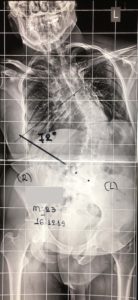

- α

- β

Εικόνα 1 (α,β,)

Παρατηρείται αριστερό Θωρακο-οσφυϊκό κύρτωμα μεγέθους 40ο περίπου μοιρών κατά Cobb επίσης δε ασυμμετρία και ανισοϋψία της πυέλου. Υπάρχουν πολλές συγγενείς ανωμαλίες των σπονδύλων (ημισπόνδυλοι σε όλη την έκταση της Σ.Σ., από τον αυχένα μέχρι το ιερό οστούν).